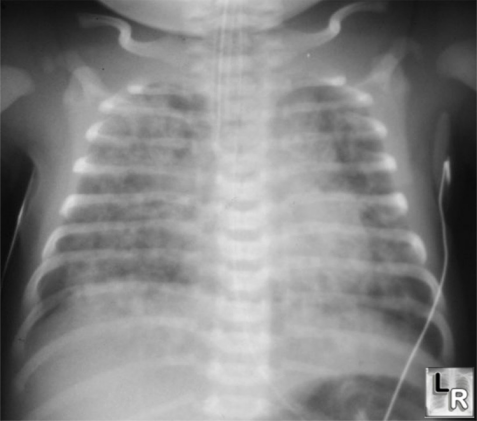

胎粪吸入

生后第一天

胸部X线检查:

对称性分布,

致密的片状 肺部浸润

部分区域充气过度